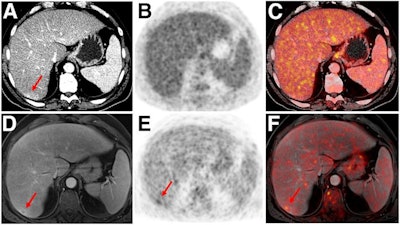

- Malignant bone disease (2.4%)

Indeterminate lesion on PET/CT classified by PET/MRI for 53-year-old man with lung cancer. Contrast-enhanced CT (A), PET (B), and fused F-18 FDG PET/CT (C) images are displayed in comparison with contrast-enhanced T1-weighted MRI (D), PET (E), and fused F-18 FDG PET/MRI (F) images. In CT (A), hyperdense, subcentimeter liver lesion (arrows) in segment VII is suggestive of transient hepatic attenuation difference or small hemangioma. As malignancy cannot be excluded, it needs further investigation. On PET/MRI, lesion is clearly classified as metastasis because of contrast enhancement and tracer uptake due to later acquisition time point. Follow-up CT confirmed diagnosis after 78 days. Image courtesy of the Journal of Nuclear Medicine.After exclusions, the researchers examined 1,003 PET/MRI scans of 918 patients. PET/MRI outperformed PET/CT in terms of providing more tumor information (26.3%), mostly in patients with malignant bone disease, followed by lung cancer, prostate cancer, and gynecologic or breast cancer. PET/MRI identified additional malignant findings in 5.3% of cases, which lead to a change in tumor, node, and metastases (TNM) staging in 2.9% of cases. PET/MRI also clearly classified indeterminate PET/CT lesions in 11% of cases.

A smaller percentage of lesions, 2.9%, were detected on PET/CT but not visible on PET/MRI. Of those lesions, 1.2% were malignant and led to a change in TNM staging in 0.5%. It should be noted PET/MRI missed a negligibly small number (0.8%) of lung metastases, which contradicts previous beliefs that the chest requires additional CT, the authors wrote. In addition, new MRI sequences such as ultrashort echo-time sequences are expected to improve lung nodule detection, which would also enhance the sensitivity of PET/MRI even further, they added.